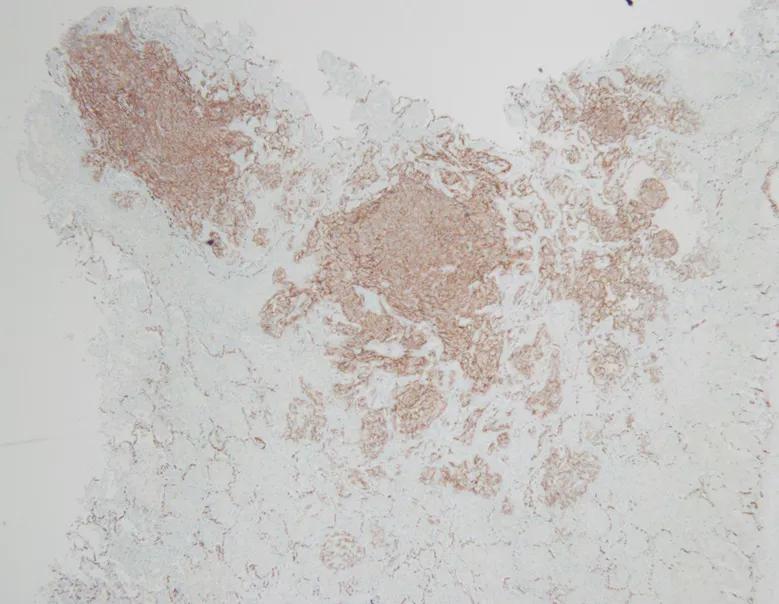

活检病理:

A 术中可见肺组织表现有弥漫性出血性病灶;B 低倍镜下病理病灶;C 高倍镜下可见大量梭形细胞;D 免疫组化可见CD34(+)、CD31(+)

术后病理:血管肉瘤

ERG(+)

CD31(+)

王岩主任(病理科)点评:

送检楔形切除肺组织一块,大体可以看到肺组织切面有凝血,并有大小不等的多枚结节。

镜下可以看到肺泡腔的弥漫出血,局部可以看到较多官腔样结构,衬覆上皮有异性性,另外可以看到成片的异性细胞在肺内多结节生长,呈梭形,可见到多量核分裂,这时候倾向为高度恶性肿瘤病变,镜下表现可排除上皮样血管内皮瘤,因为后者呈低度恶性、轻度异型性、核分裂相不如该患者明显。该患者组织学表现在病理上有以下考虑:肺腺癌?恶性间皮瘤?恶性黑色素瘤?血管肉瘤?硬化性肺细胞瘤?借助免疫组化结果CK(-)、TTF-1(-)Ki67(70%+)可以排除上皮样血管内皮瘤、肺腺癌、恶性间皮瘤、硬化性肺细胞瘤。HMB45(-)、melan- A(-)排除恶黑肺转移可能性。CD31(+)ERG(+)支持血管肉瘤的病理诊断。